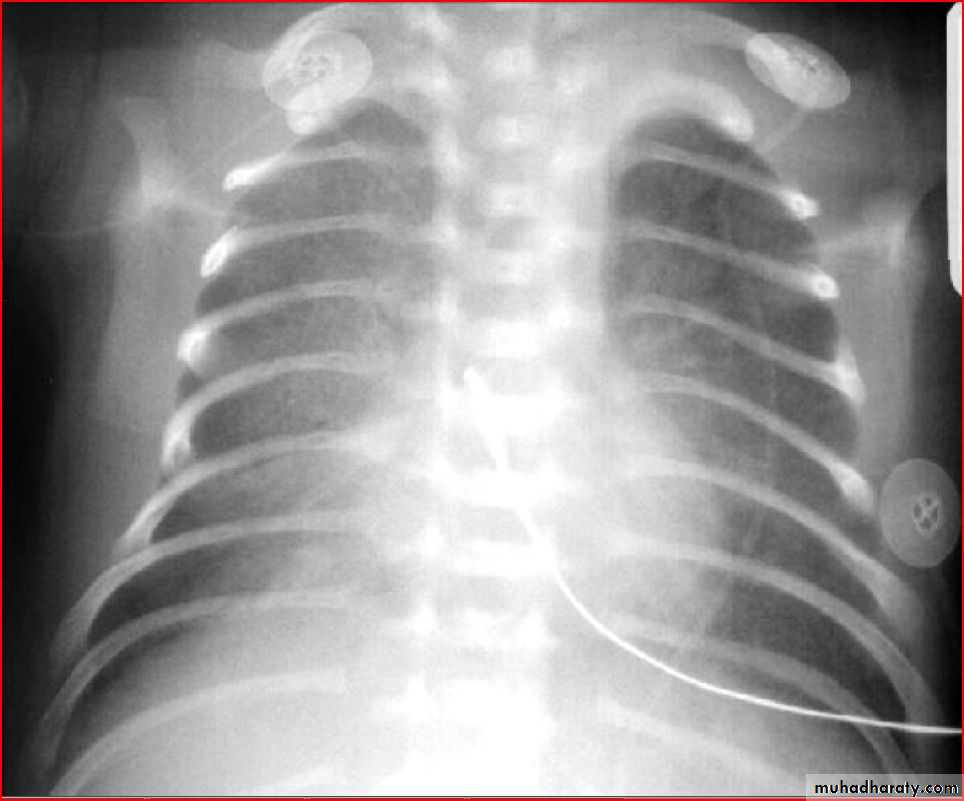

Normal xray after FB removalRds ( fine reticulo-granular pattern ) كعب البطل

Ground glass apperance